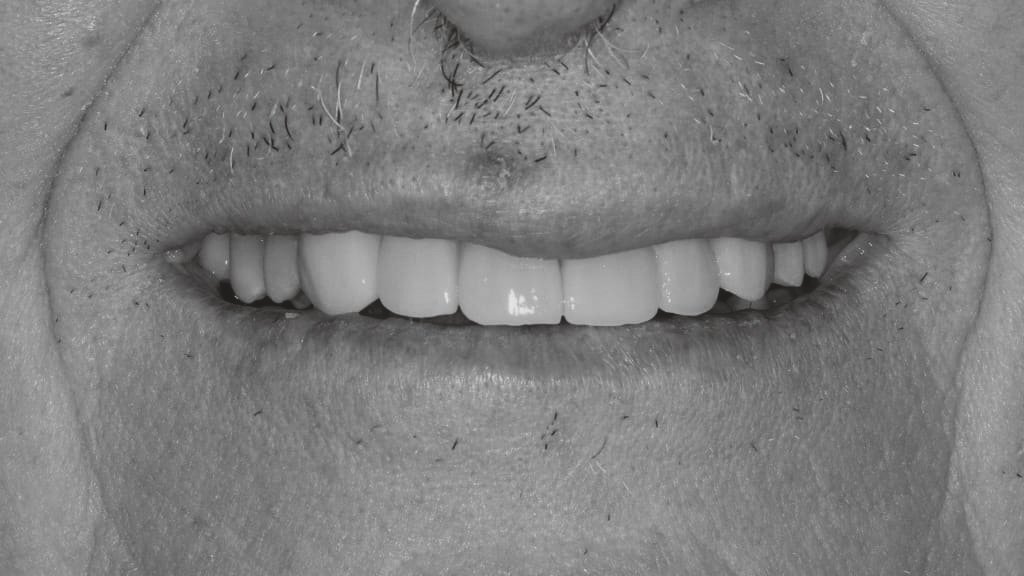

Antes y después en nuestros tratamientos dentales

A continuación te exponemos algunos de nuestros casos de antes y después en implantes dentales, ortodoncia y estética dental.

Antes y después en Implantes Dentales

En las imágenes de antes podemos ver a pacientes con dientes faltantes o dañados, lo que les dificultaba sonreír con confianza y realizar actividades cotidianas como masticar. Sin embargo, después de la colocación de los implantes dentales, podemos ver cómo sus sonrisas han cambiado completamente.